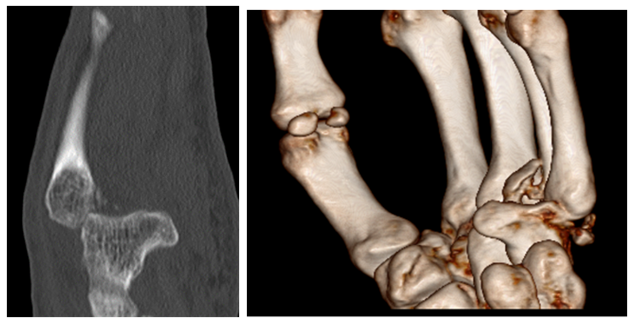

The use of CT and MRI in the acute setting may be essential to confirm dislocations which may be unclear on plain radiographs.19,24 These modalities allow for the assessment of the joint articular surfaces25 and in the case of MRI the soft tissues are also delineated as well. The information thus obtained may influence the surgical approach. Open procedures may be preferable to closed reductions in the face of concomitant ligament ruptures requiring repair for CMC stability.20 Since the wrist is a peripheral joint, the radiation dose of a CT is minimal26 thus justifying use of this modality when clinically indicated.

MRI has been shown to be superior to CT in the detection of purely trabecular fractures and in delineating other injuries such as ligament rapture which may play a crucial role in the selection of the best way to treat these dislocations.27

CT scanning may be superior in achieving a clearer picture of the articular surface relationships.21,25  Moreover, new CT imaging techniques use significantly reduced patient doses of radiation and allow for 3D reconstructions which aid diagnosis and surgical planning25 (Figure 5).

Figure 5 CT images and 3D reconstructions demonstrates relationship of articular surfaces better than plain radiographs.